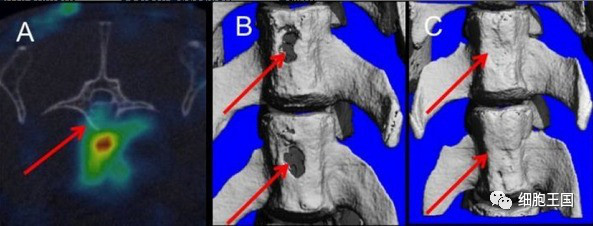

实验室的研究人员给予实验动物对象为期 21 天的甲状旁腺激素注射,同时使用取自成年人骨髓 5 个单位的干细胞注射。结果表明,联合治疗可以显著增强干细胞的迁移到骨折部分,并且促进骨折处形成新的、健康的骨骼(图 1)。

图1  A 干细胞靶点的脊柱骨折;B 两个脊椎骨折;C 干细胞与甲状旁腺素治疗 8 周后修复的脊柱